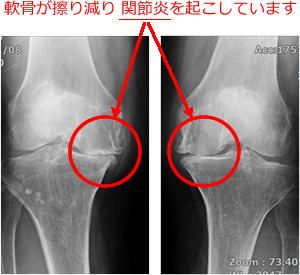

変形性膝関節症や関節リウマチなどにより変形した関節をセラミック、ポリエチレンなどでできた人工膝関節で入れ替えることで痛みがなくなります。

図1:手術前 |